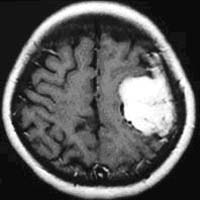

髄膜腫

血管に富んだ腫瘍に対して、手術前に腫瘍を栄養する血管に対して塞栓術を施行しています。